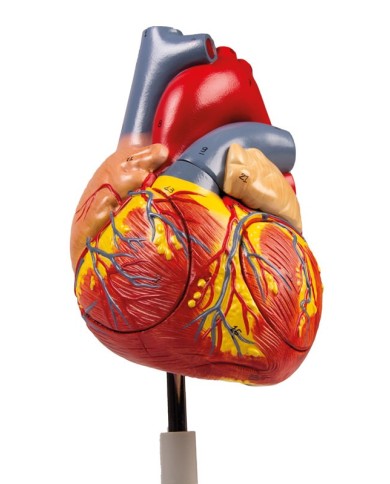

Modello di cuore di alta qualità scomponibile in 5 parti

Modello di cuore di alta qualità scomponibile in 5 parti

Modello anatomico di cuore, ingrandito 2 volte, su cavalletto

Questo modello dettagliato mostra, oltre alle strutture anatomiche del cuore, anche una parte del diaframma (base)